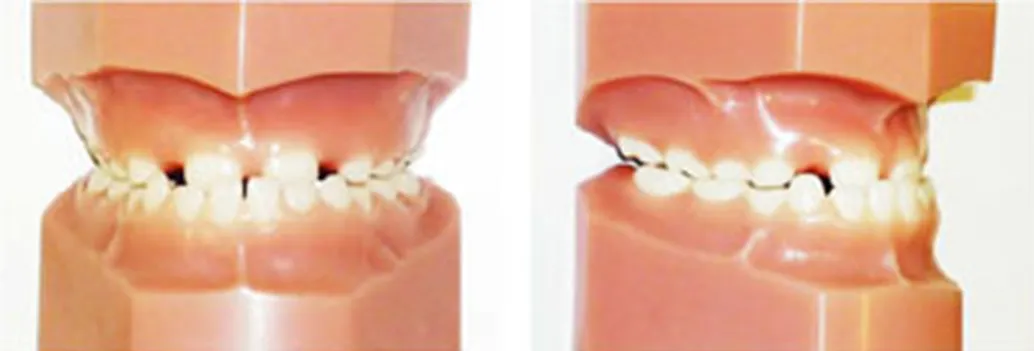

小児の不正咬合の分類

乱杭(らんぐい)歯(叢生)

顎が小さいことで歯が並ぶスペースが不足し、歯が重なり合ってでこぼこに生えています。

出っ歯(上顎前突)

上の前歯や上顎が前方に突出しています。

受け口(下顎前突・反対咬合)

下の前歯や下顎が、上の前歯よりも前方に突出しています。

開咬

奥歯を噛んでも上下の前歯が閉じず、隙間から舌が見える状態です。舌癖が影響していることもあります。

交叉咬合(こうさこうごう)

一部の噛み合わせが反対(下の歯が上の歯より前に出る)になっており、上下の前歯の中心がずれている場合もあります。その影響で、下の横の歯や下顎が前に出て見えることがあります。

過蓋咬合(かがいこうごう)

上の前歯が下の前歯を深く覆い、下の前歯がほとんど見えない状態です。出っ歯の方に多く見られる状態です。